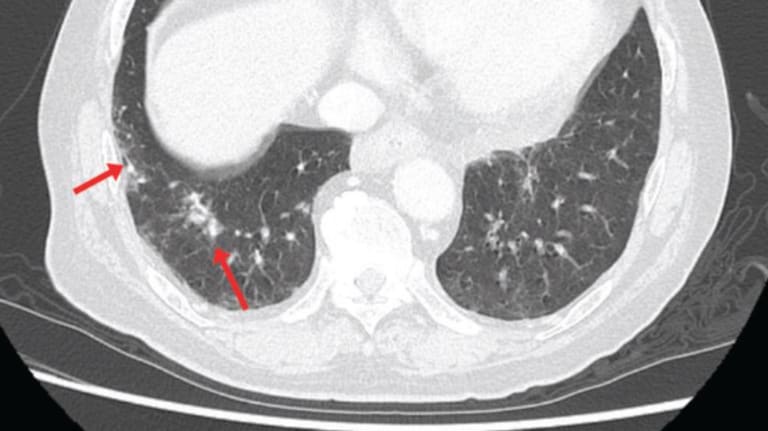

Abb. 1b: Die Computertomographie zeigt körnige und interstitielle Schatten in der Lunge.

© Navano T et al. CMAJ 2025; 197(31): 1004-1005